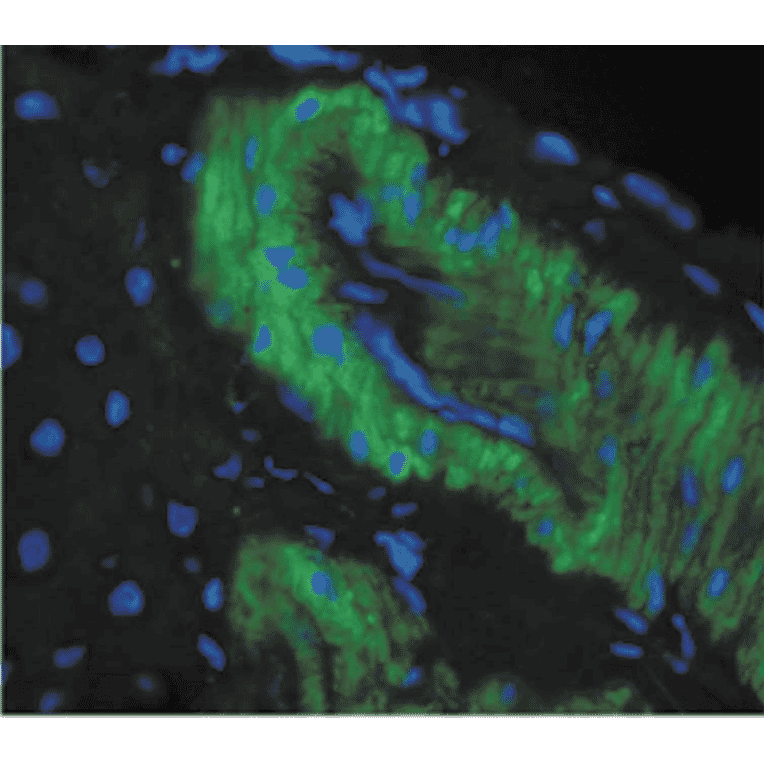

Immunohistochemistry analysis of mouse backskin, fixed in Bouin's fixative solution and paraffin-embedded. The Primary Antibody used was Anti-Nitrotyrosine Antibody [39B6] (A304794) at 1:100 for 1 hour at room temperature. The secondary antibody used was FITC Goat Anti-Mouse (green) at 1:50 for 1 hour at room temperature. Backskin obtained from transgenic mice.